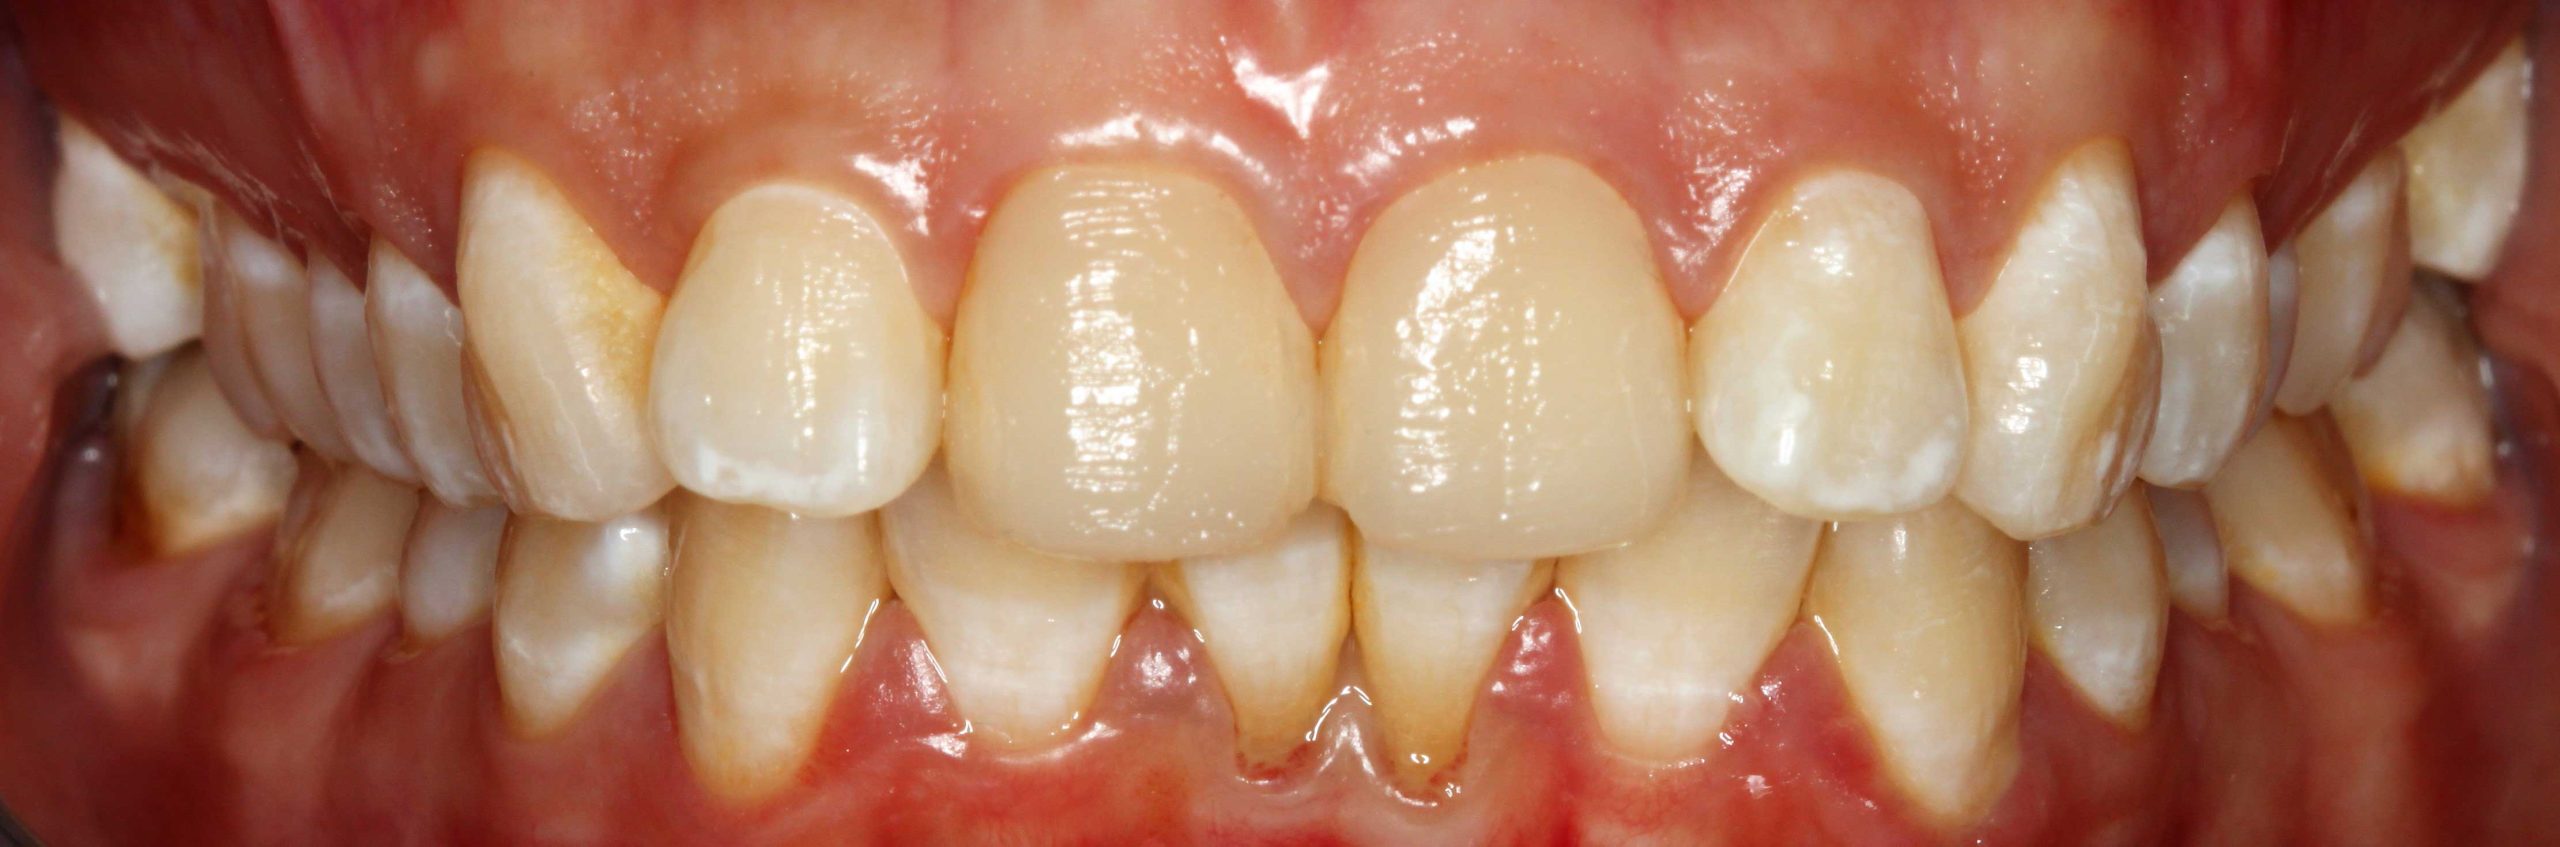

Blanqueamiento

Dra. Carmen Feito Bárcena

El paciente vino con una sonrisa con coloración más apagada y manchas. Tras el tratamiento con un blanqueamiento dental, se muestra una clara mejoría en luminosidad, con un aspecto homogéneo.